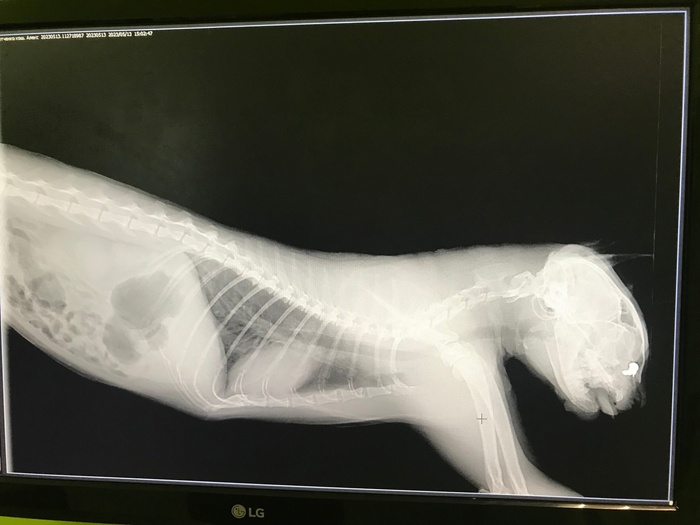

Четвертая. Амели. Тоже выбросили, как ненужный хлам. У Амели ещё и ОХД до кучи.